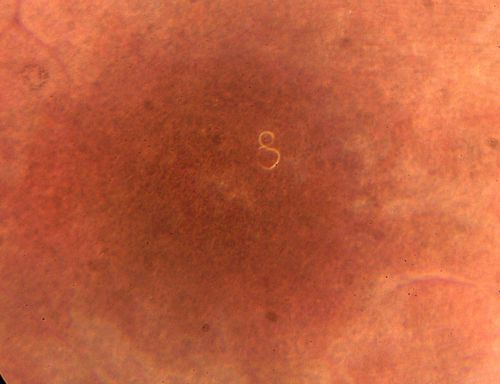

DUSN - Diffuse Unilateral Subacute Neuroretinitis - Nematode